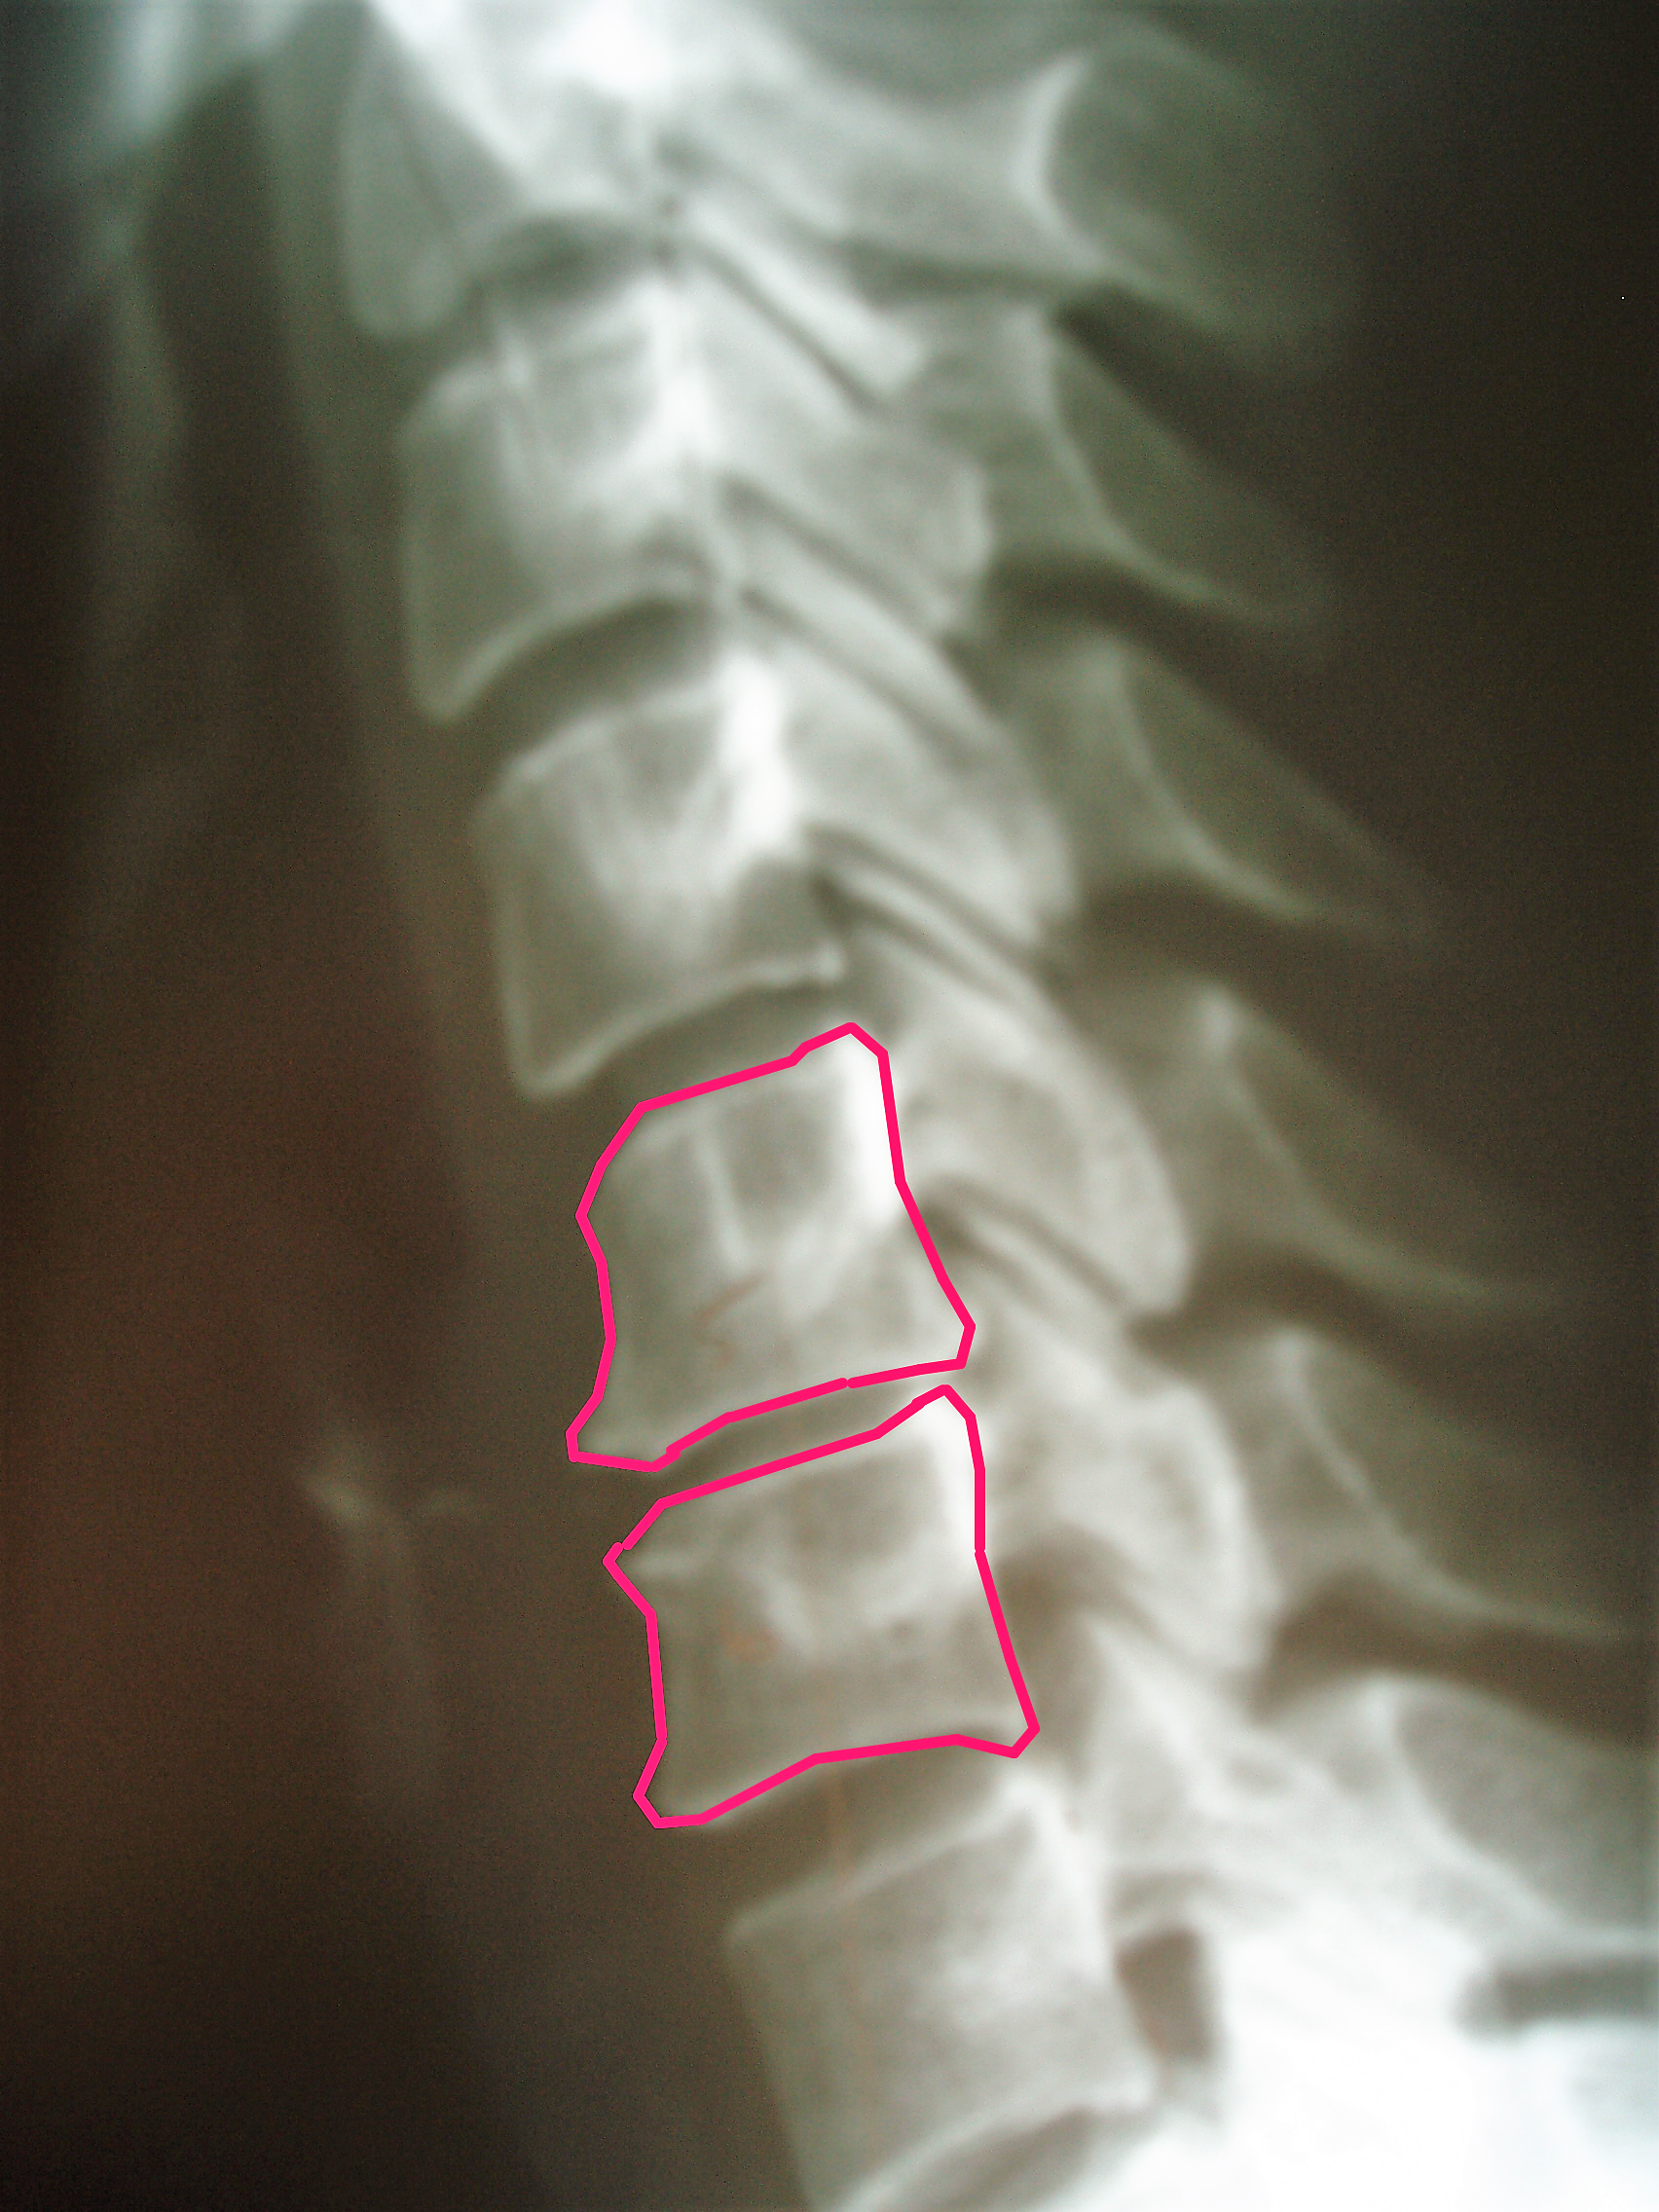

normal x ray post

Got Curve?

Normal Neck and Low Back Curve (lordosis) is 42 and 40 Degrees respectively, from the side.  What is yours?  40, 30, 12 or maybe even 0 degrees?  You should know.  It could be ...